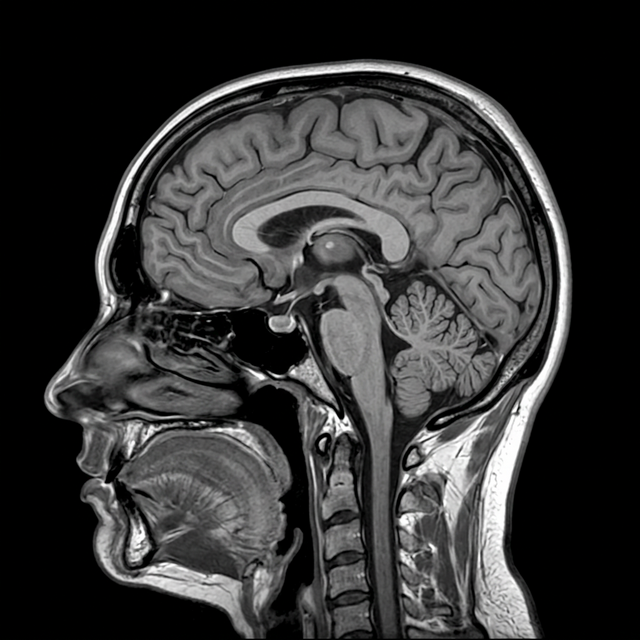

Review MRI and CT scans natively: no third-party viewer, no file transfers. Pan, zoom, and annotate in real time.

Pull up 3D spinal or cranial models side-by-side with patient imaging. Explain findings to patients in 3D during the consultation.

DOE, JOHN

ID: 4492-AX-22

MR / SAGITTAL

MAGNETOM EXPERT

PHILIPS_MEDICAL

14-OCT-2025

12:54:35

S1 / L24

ST: 10.00mm

RT: 20.00ms

THK: 1.5mm

L: 350.00

W: 630.00

Z: 206%

L4-L5 Protrusion

AI INFERENCE

"Focal posterolateral disc protrusion at L4-L5 level with suspected dural sac impingement."